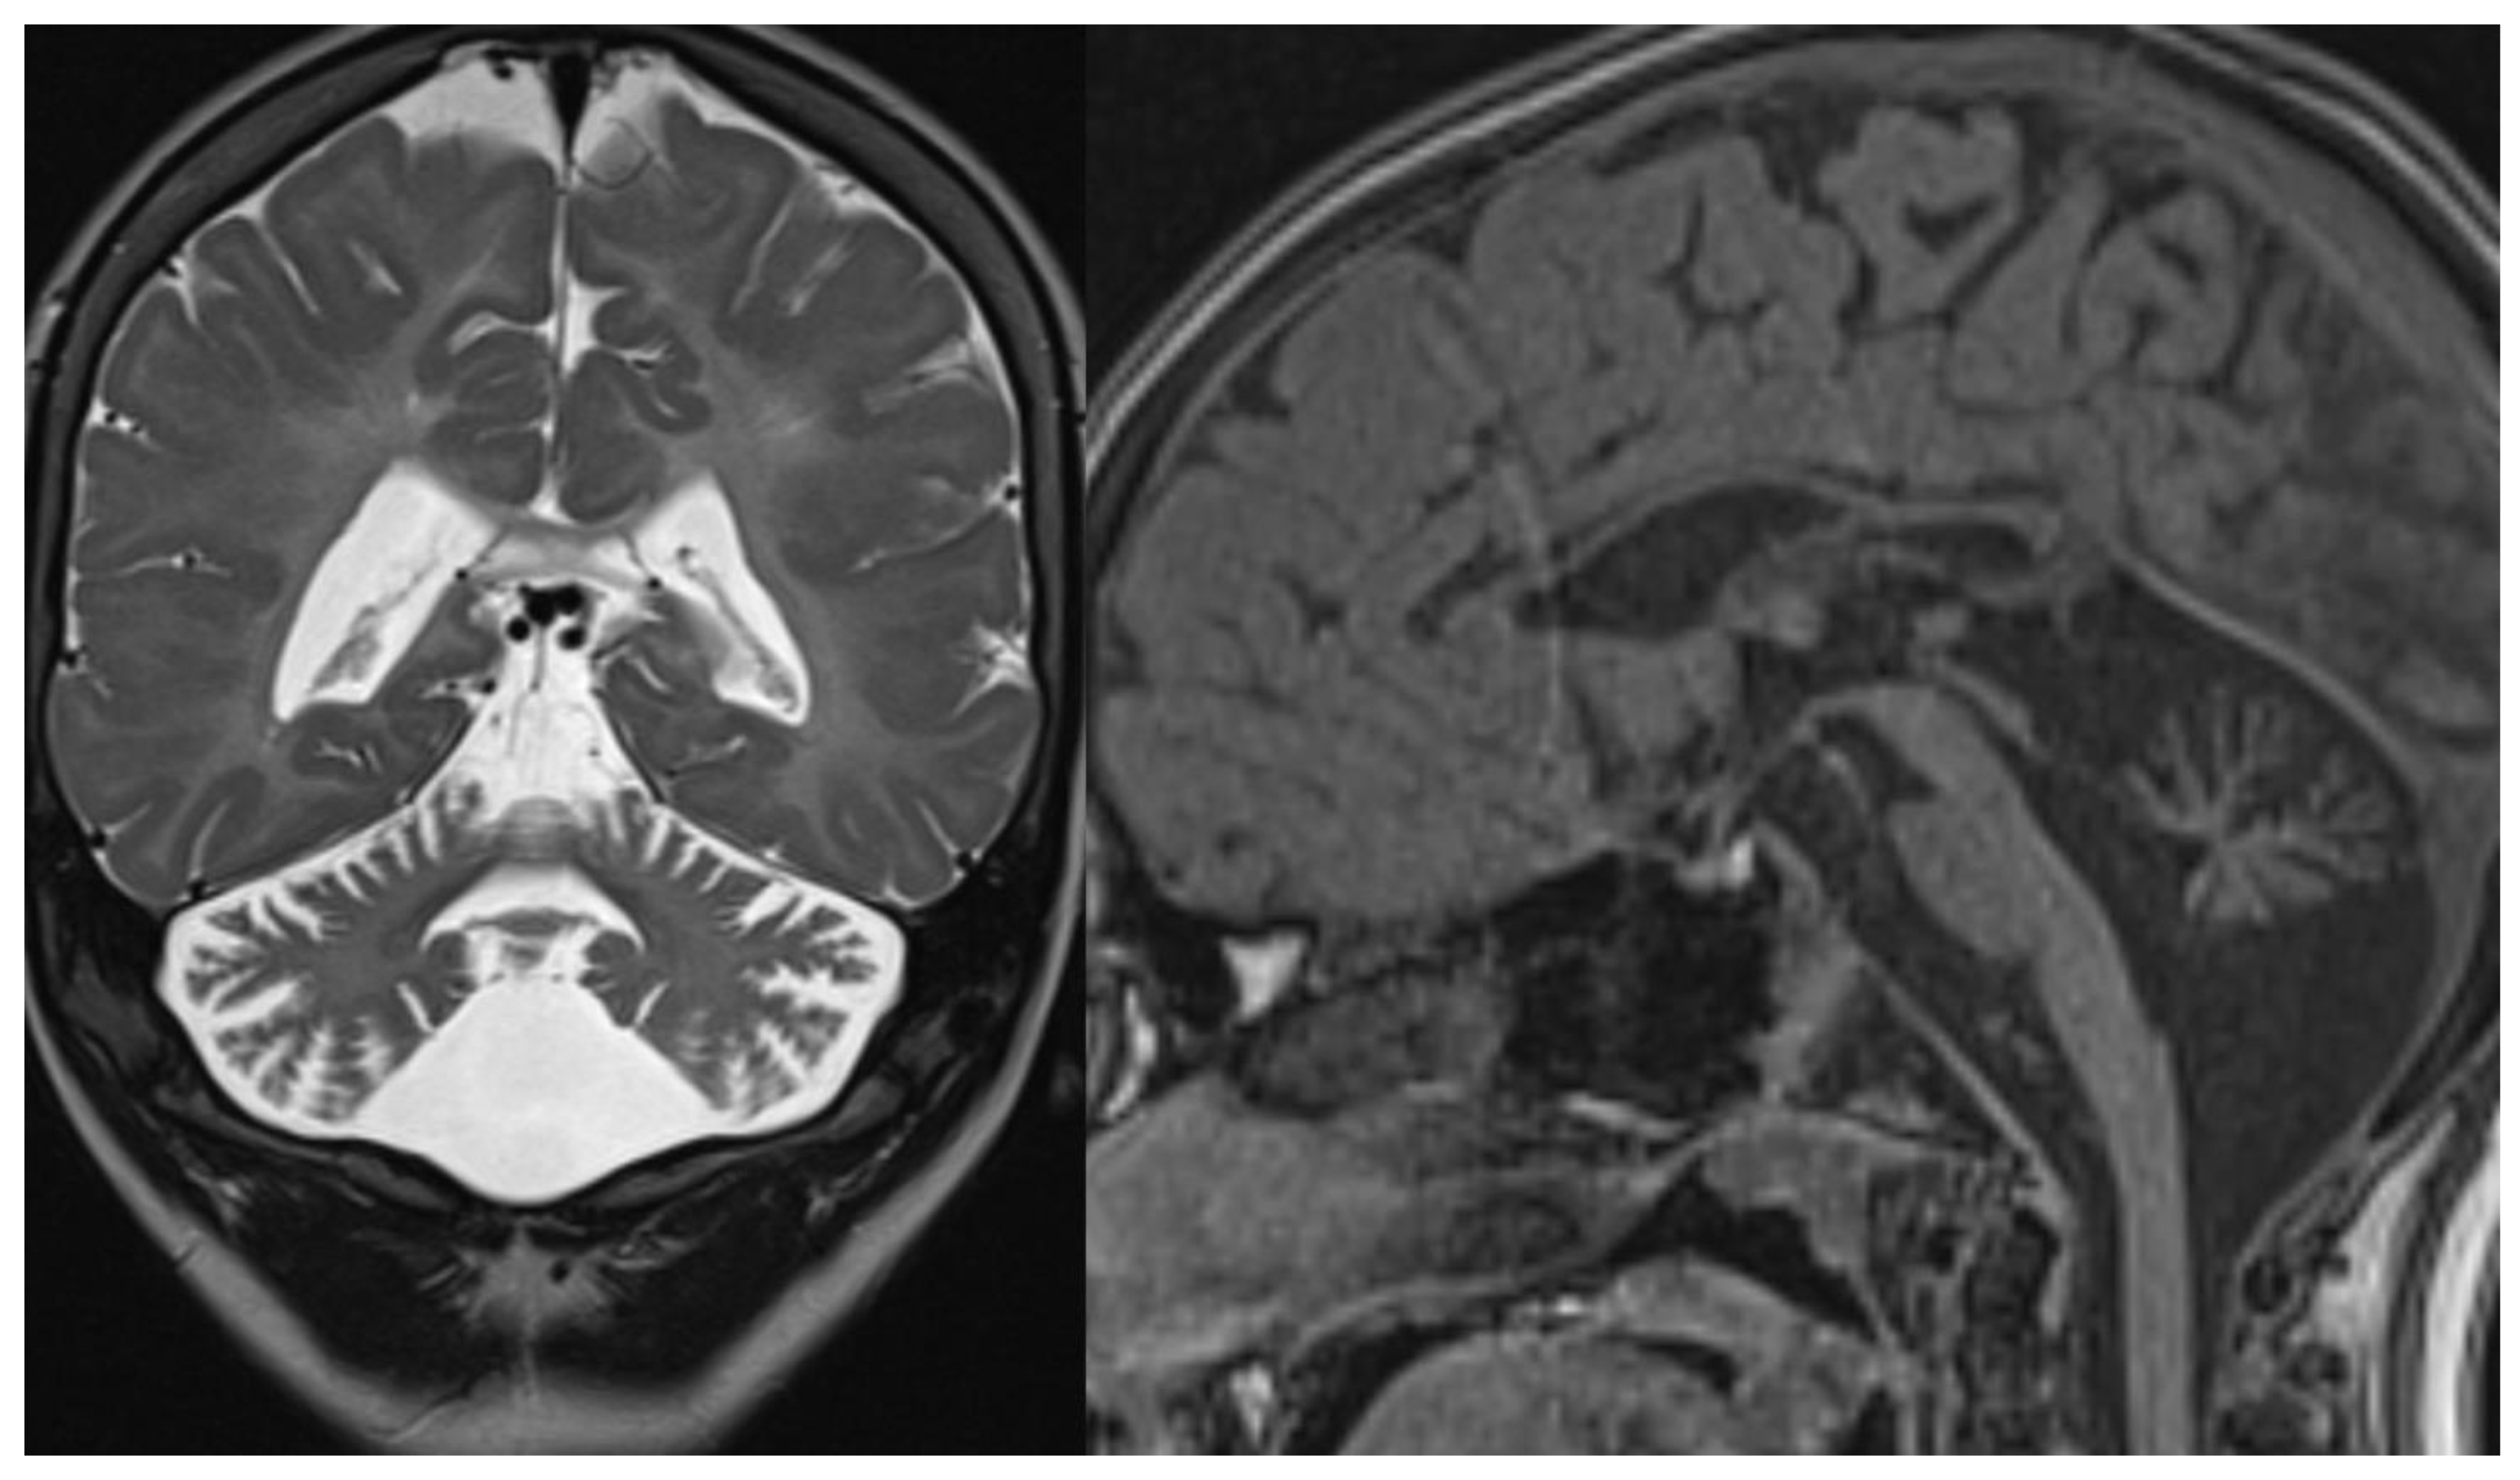

Isolated or predominant cerebellar volume loss due to cerebellar hypoplasia or, more frequently, progressive cerebellar atrophy are common neuroradiological features in children with various mitochondrial disorders: complex I, complex II, complex III and complex IV deficiency, isolated or combined, multiple respiratory chain defects (RCDs) and partial coenzyme Q10 deficiency [44] (Figure 8).

Figure 8.

Coenzyme Q10 deficiency. Brain MRI scan of a 15-year-old girl. MR images demonstrate not specific diffuse cerebellar atrophy and a normal volume of the brainstem.

Coenzyme Q10 transfers electrons along the respiratory chain; among other clinical manifestations, Coenzyme Q10 deficiency has been associated with cerebellar ataxia [45]; 13 genes encode proteins involved in its biosynthesis, but only mutations in 10 genes have been associated with diseases. One of the most well-documented is mutations in the COQ8A gene (formerly ADCK3). In these patients, cerebellar atrophy is an almost universal finding [46].

CACNA1G calcium channel is known to cause adult-onset spinocerebellar ataxia [42]; recent works report cerebellar ataxia associate with mutations in this gene [48,49]. MRI shows cerebellar atrophy [49] (Figure 9).

Figure 9.

CACNA1G mutation. Brain MRI scan of an 11-year-old girl. MR images demonstrate not specific diffuse cerebellar atrophy.